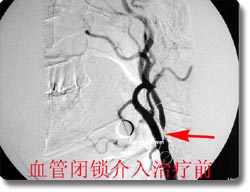

开展了脑动脉瘤、脑血管畸形、颈内动脉海绵窦瘘、脊髓血管畸形的神经介入治疗和恶性肿瘤的次选择性化疗,尤其是对巨大动脉瘤的栓塞成功率达到国内领先水平。同时开展了脑动脉瘤、动静脉畸形、高血压脑出血的手术治疗和血管闭塞性疾病的颅内外搭桥手术、颈内动脉内膜切除术、急性栓塞的溶栓治疗术、血管内支架放置手术,颅内动脉瘤电解可脱性螺旋圈(CDC)治疗,先后收治病人4000余例,积累了丰富的经验,为脑血管狭窄、脑供血不足及脑血栓病人的康复提供了有力保证。介入治疗具有不出血、无感染、损伤小、风险小、恢复快的优点,是脑血管疾病病人的理想选择。2003年,与北京宣武医院强强联合成立了北京市脑血管病中心重庆分中心。2005年成功地承办了第七届全国神经外科血管内治疗研讨会,受到了与会专家的一致赞誉。